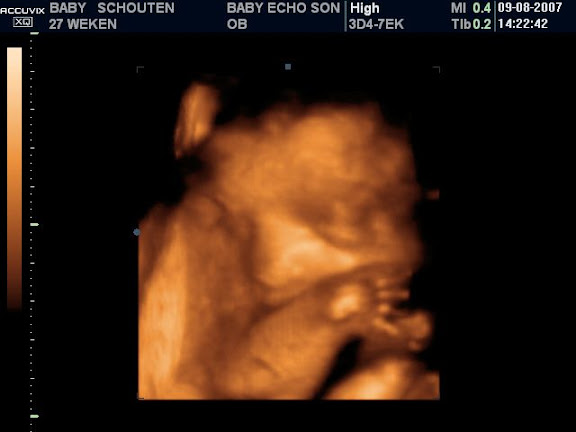

wat is t verschil tussen zo'n 3 en 4D echo?

Maneki.Nekodinsdag 30 oktober 2007 @ 20:05

4D is bewegend 3D. De term op zich bestaat eigenlijk niet, maar wordt er wel voor gebruikt

4D is toch bewegend 3D?

cool zie je dat hummeltje dan echt zwaaien, zwemmen etc

Ja! Er werd druk met een armpje gewapperd en iedereen kon live meegenieten dat ik een schop kreeg haha